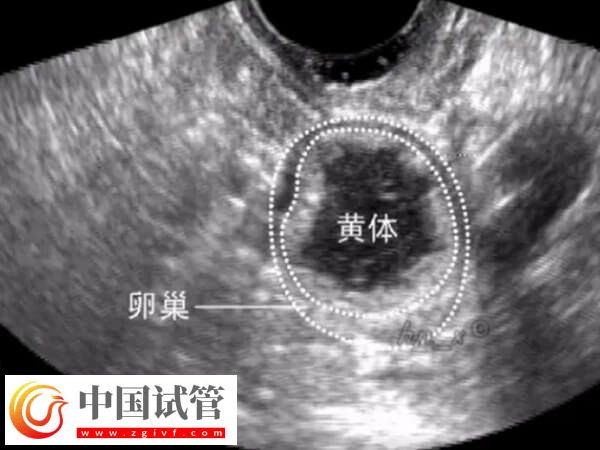

什么是黃體殘留

排卵后形成的黃體是一個含有滿足受精卵的營養(yǎng)素的蛋白質團。這個結構會釋放出大量的孕酮和雌二醇,為身體準備迎接懷孕提供支持。如果在排卵期間使用了藥物進行控制,以刺激卵巢產(chǎn)生更多的卵子,黃體就可能在患者體內止于時間較長,也就是產(chǎn)生所謂的“黃體殘留”。